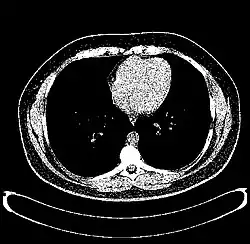

CT scan of the thorax with window level set to 0 HU (water)

CT scan of the thorax with window level set to 60 HU (liver)